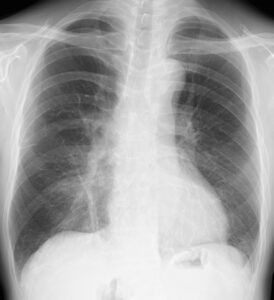

増悪する夜間咳嗽から心不全を心配してNT-proBNPを測定したところ、87.6pg/mlとカットオフの125未満だったので、心不全ではないと診断し、抗菌薬を追加したところ改善しました。

抗菌薬投与後の胸部レントゲン

右下肺野は改善